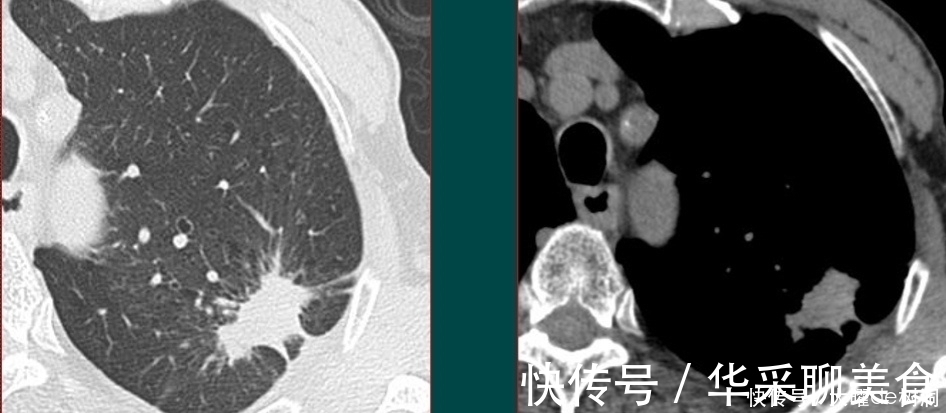

一般来说,各种方式发现了肺部小病灶,首先都应做一个胸部螺旋CT,如果是实性结节,还需要增强扫描观察病灶的血供特点。

胸部CT配合增强扫描,加上肿瘤标志物检测等临床资料,可以明确大部分恶性肿瘤。

文章插图

像这个病灶,混合磨玻璃结节伴有胸膜牵拉,CT就可以明确为肺癌。

而对不典型病灶,可能需要先抗炎治疗后复查,或者进一步穿刺、支气管镜、甚至PET-CT等方法明确。

像这位78岁的老爷子,左肺不规则结节,周围有毛刺,伴有胸膜牵拉,高度怀疑肺癌。

但是做了增强扫描发现病灶没有任何强化,提示这是一个结核球,良性。

后来穿刺证实确实是结核性肉芽肿,避免了挨一刀。

(这个病例是豪大夫的师傅,山东肿瘤医院的黄教授提供的)